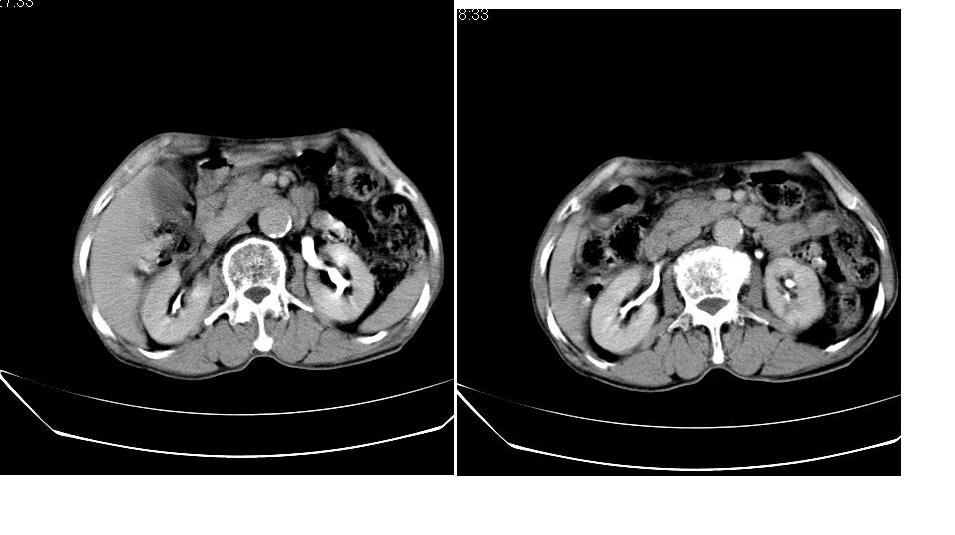

男,76岁,上腹部疼二天来就诊,彩超提示肝左叶占位,随后做上腹部ct平扫,今天做上腹部ct增强扫描,手工推药,效果不好,请谅解。

1)肝右叶前段低密度灶,不排除肝癌可能;建议查afp。2)右肾上极囊肿。

肝内胆管积气扩张,胆囊增大,肝右前叶低密度灶,逐渐强化,一元论,胆系感染,局限性肝脓肿;右肾囊肿。

考虑肝s4段肝脓肿可能?未排除肝癌。右肾上极囊肿。